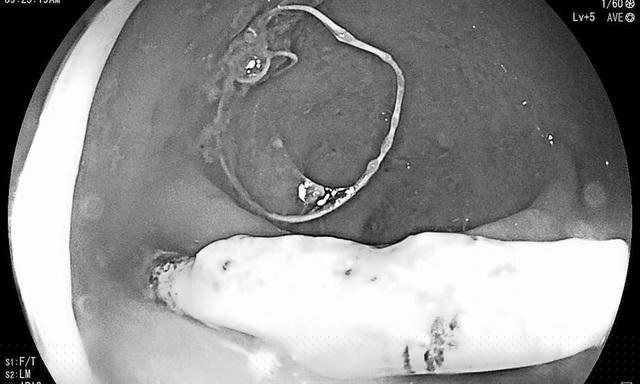

Bệnh viện Hữu nghị Việt Nam - Cu Ba Đồng Hới ( Quảng Bình) cho biết họ vừa tiếp nhận một bệnh nhân nữ 26 tuổi nội soi đại tràng. Bác sĩ phát hiện một vòng tránh thai nằm lạc chỗ, đâm xuyên thành trực tràng. Một nửa chiếc vòng nằm trong ổ bụng, nửa còn lại nằm trong lòng trực tràng. Ngay lập tức bệnh nhân được chỉ định phẫu thuật lấy chiếc vòng.

Vòng tránh thai đâm thủng trực tràng. (Ảnh: Bệnh viện cung cấp)

Bác sĩ bệnh viện Hữu nghị Việt Nam - Cu Ba Đồng Hới chia sẻ, Vòng tránh thai lạc chỗ nếu không phát hiện kịp thời sẽ dẫn đến hậu quả ruột mạc nội quấn lấy vòng, thủng ruột, viêm phúc mạc, nhiễm trùng huyết. Đặt vòng tránh thai là một trong những biện pháp ngừa thai hiệu quả lên tới 97% và được nhiều phụ nữ lựa chọn. Vòng tránh thai là một thiết bị nhỏ (thường có hình chữ T) được đặt vào tử cung, hiệu quả ngừa thai kéo dài.